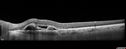

74 year old man caucasian man: The patient started having trouble with his vision after his stroke 10/9/17. He noticed after recovery that his peripheral vision had declined. He doesn't notice a difference between his two eyes. He has been having trouble focusing together his two eyes. After his stroke he was not able to read. He could trace letters but not see. He is having speech and occupational therapy at the moment. VA OD: sc20/125-2 PH20/125-2 NccJ1+ VA OS: sc20/63-2 PH20/100-2 NccJ1 Vision improved to 20/20 with Lucentis

Polypoidal Choroidal Vasculopathy Left Eye342 views74 year old man with vision loss to 20/100 over a few months. He improved to 20/20 with Lucentis. The color and ICG show the polyps.00000